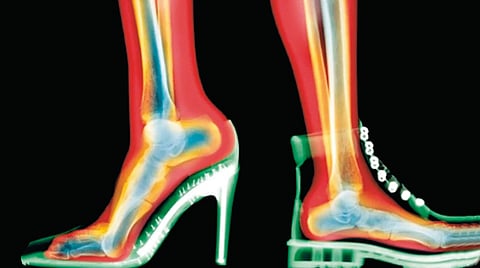

उंच टाचांच्या चप्पला दिसायला मोहक असल्या, तरी पायांसाठी त्या सर्वाधिक हानिकारक ठरतात. टाच जितकी उंच तितके शरीराचे वजन पुढील भागावर जास्त पडते आणि बोटांवर ताण येतो. त्यामुळे पायाच्या पुढील भागात तीव्र वेदना व सूज, मोठ्या अंगठ्याजवळ हाड उभारले जाणे म्हणजेच गोखरू, बोटे वाकडी होऊन दाबली जाणे म्हणजे हॅमरटो, टाच व घोट्यात वेदना निर्माण करणारा अकिलीज टेंडनचा ताठरपणा तसेच चुकीच्या देहबोलीमुळे कंबर व गुडघेदुखी अशा समस्या वाढतात. टाच जितकी उंच आणि तळ जितका पातळ तितके नुकसान अधिक होते.